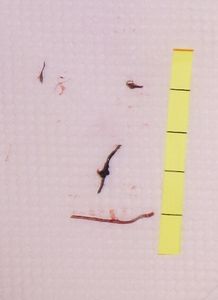

2018年3月13日,当院を受診。数箇所,肉芽形成を伴う深い瘻孔を認め,ハイドロコロイド被覆材を利用したナイロン糸ドレナージを行い,ズイコウパッド

で被覆(その後,ナイロン糸ドレナージをしなくても良好なドレナージが得られることがわかり,ドレナージは中止した)。

その後は2~4週間に一度受診してもらい,創内を探って縫合糸を見つけては除去している。